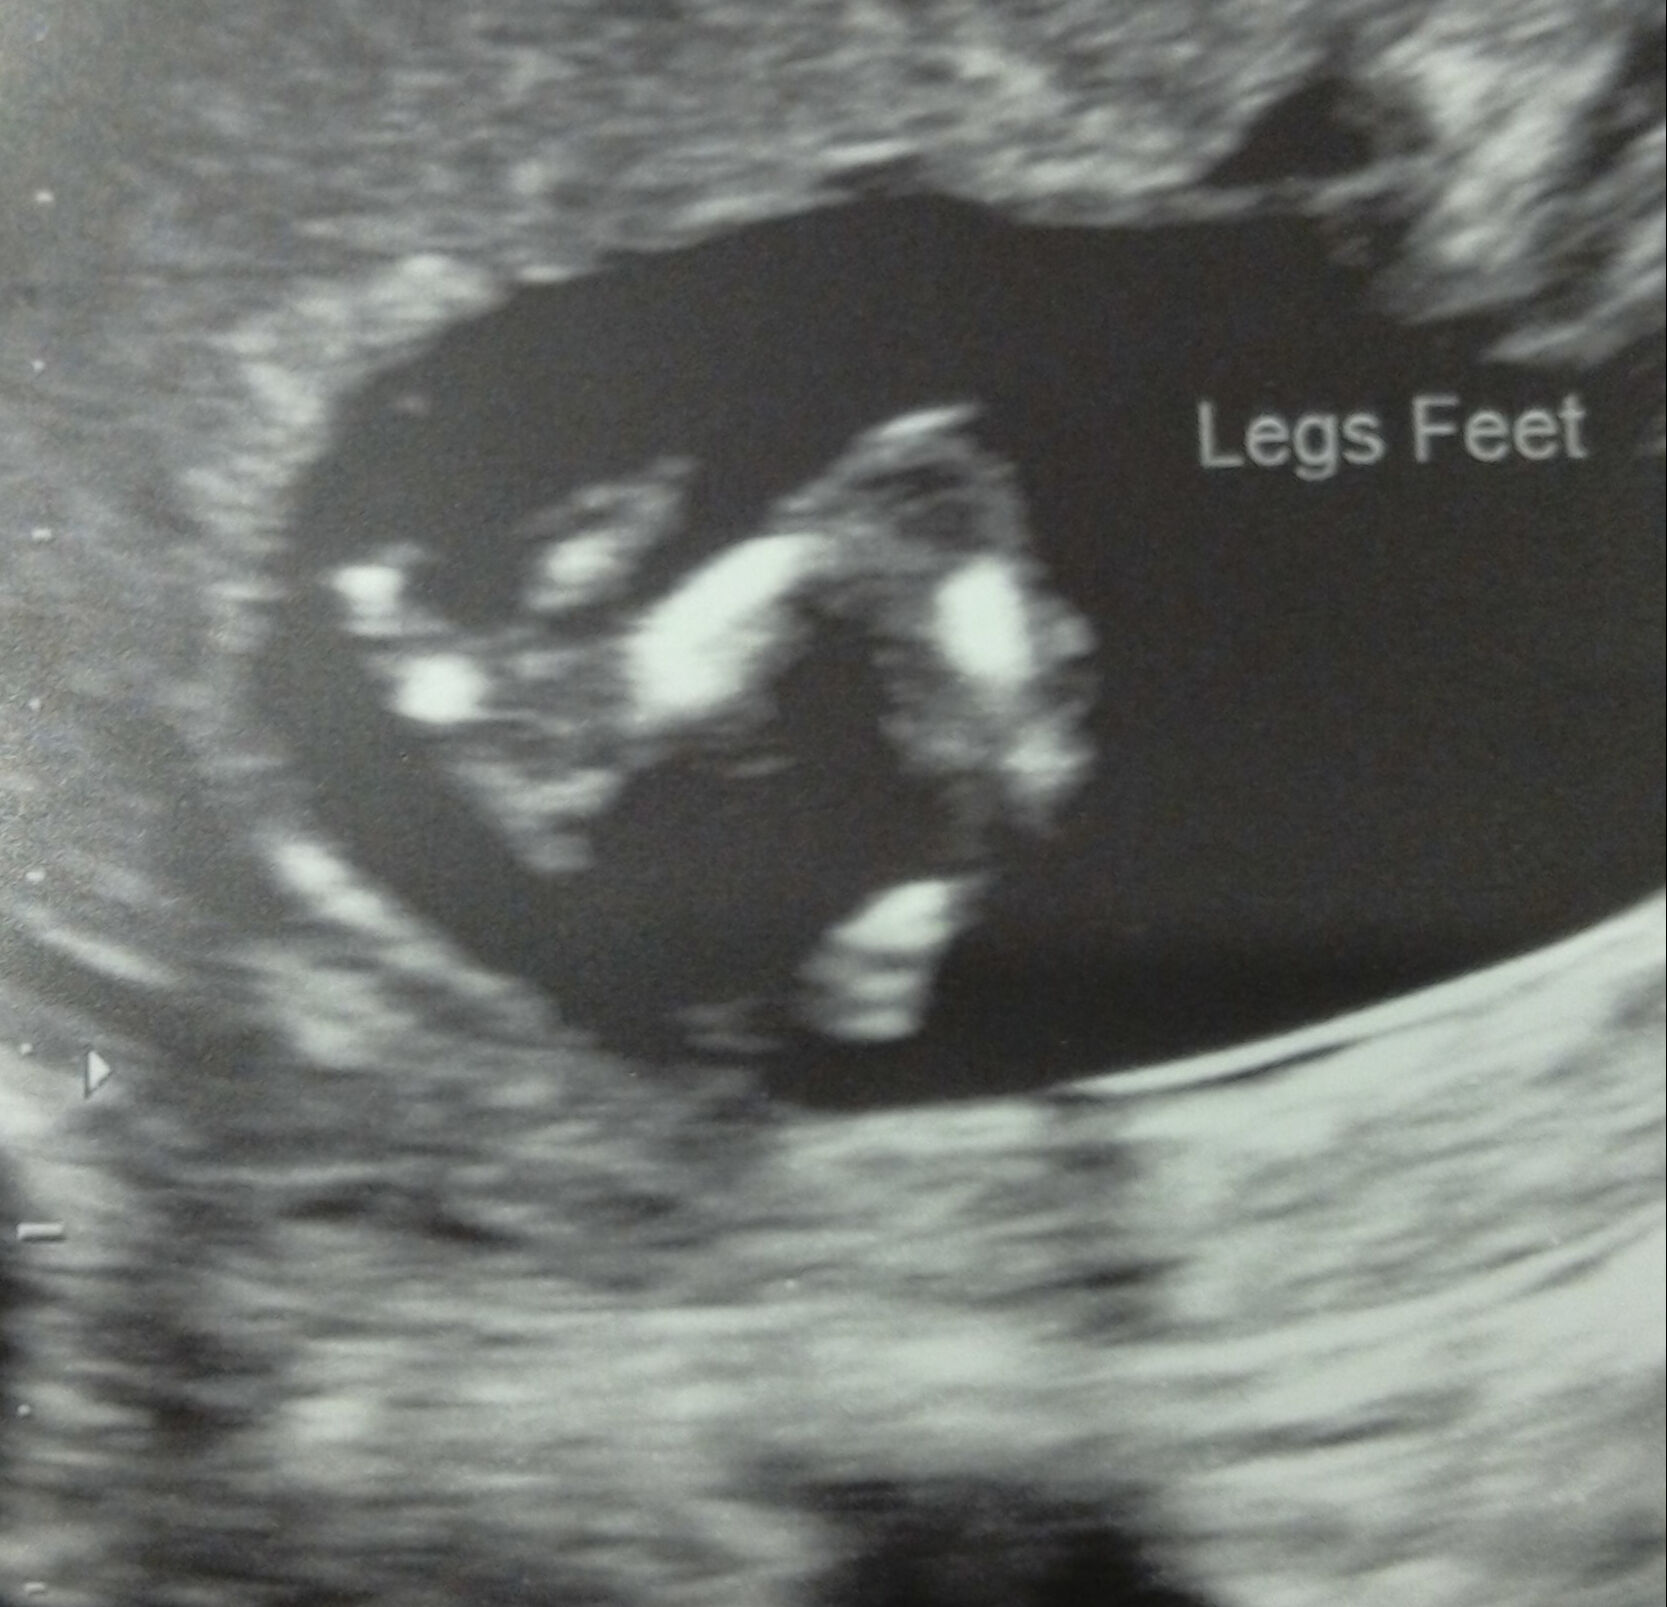

Pictures from my 12 week scan. Baby measured 13 weeks 1 day. Don't think there is any nub shots but all guesses welcome. Thanks for looking, Emma x xAttachment 29880

Another picAttachment 29882

One more xAttachment 29883